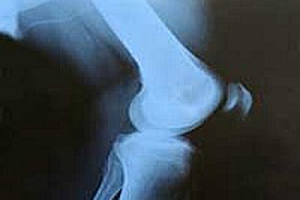

Kemik erimesini önlemek için

Dikkat! Kemik erimesine neden oluyor